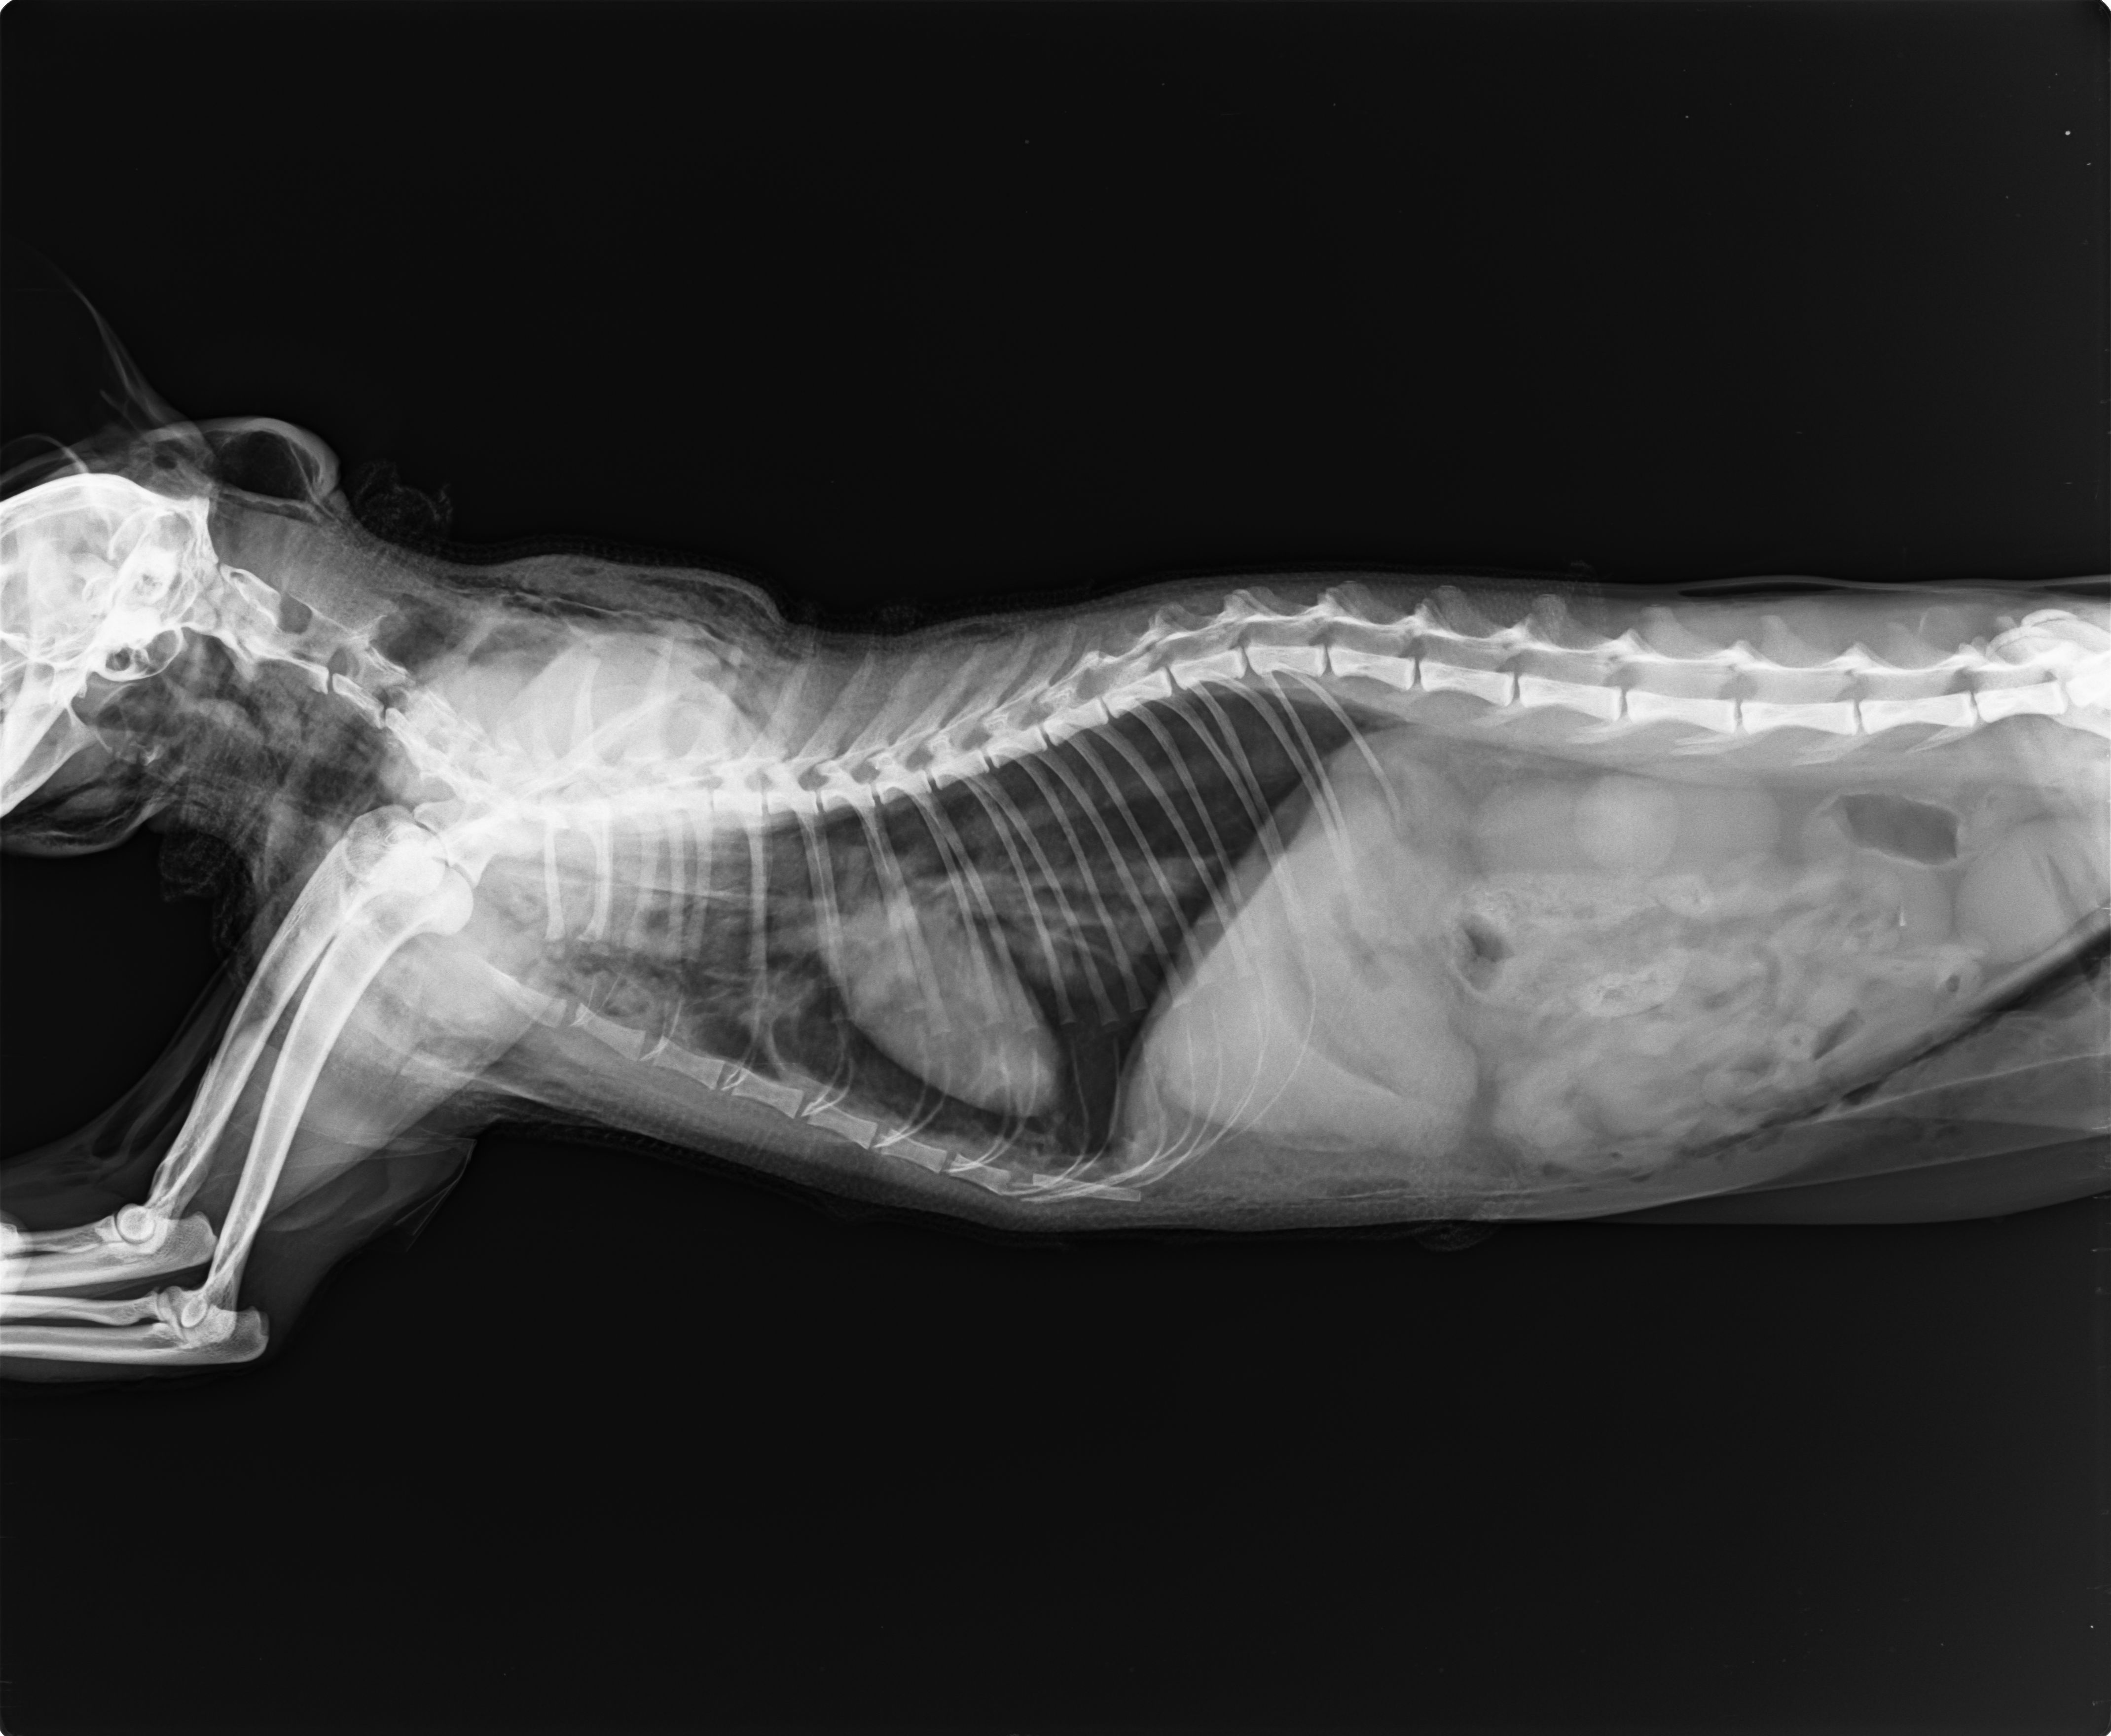

主題: 被狗咬傷導致氣胸的黑芝麻醫助案 申請者姓名: Jill Ringo 花色: 申請日期: 2013-12-09 14:10:23 申請者部落格: http://jilltgh002.pixnet.net/album 申請者臉書網址: https://www.facebook.com/jill.ringo 所在縣市/合作醫院: 台北市/極光動物醫院 治療費用: 28060元 需求人數: 30人 已結案 (2014-01-10 17:47:14) 報名人員: Jill Ringo(代Saigo Shi報名) x2(已付款)、周先媛 x2(已付款)、傻傻(已付款)、Joe Hook(已付款)、陳璇璇(已付款)、麵貓匪(已付款)、何偉靖(已付款)、曾亭亭(已付款)、陳小橘 x2(已付款)、J(已付款)、vivian(已付款)、Angel Liao(已付款)、wubaimi(已付款)、王大咪(已付款)、豬小勳(已付款)、謝佳紋(已付款)、Wanhua Chan(已付款)、megumi(已付款)、貓小玉(已付款)、Kuen-Lin Tsai(已付款)、Daisy Juang(已付款)、Nancy(已付款)、Ping Meng(已付款)、姬琳、詹曉青(已付款)、詹曉青、詹曉青、Fei Wang(已付款)、eleanore(已付款)、戀糖bear(已付款)、 候補人員: 動物病情說明: 疑似被浪狗狗咬傷的黑芝麻轉院後仍先住氧氣房,

轉院隔天醫生再拍X光,氣腫情狀有改善,

心臟也回到正確位置,表示內部的氣體有排出,

且沒有再有氣體進入,是好消息。